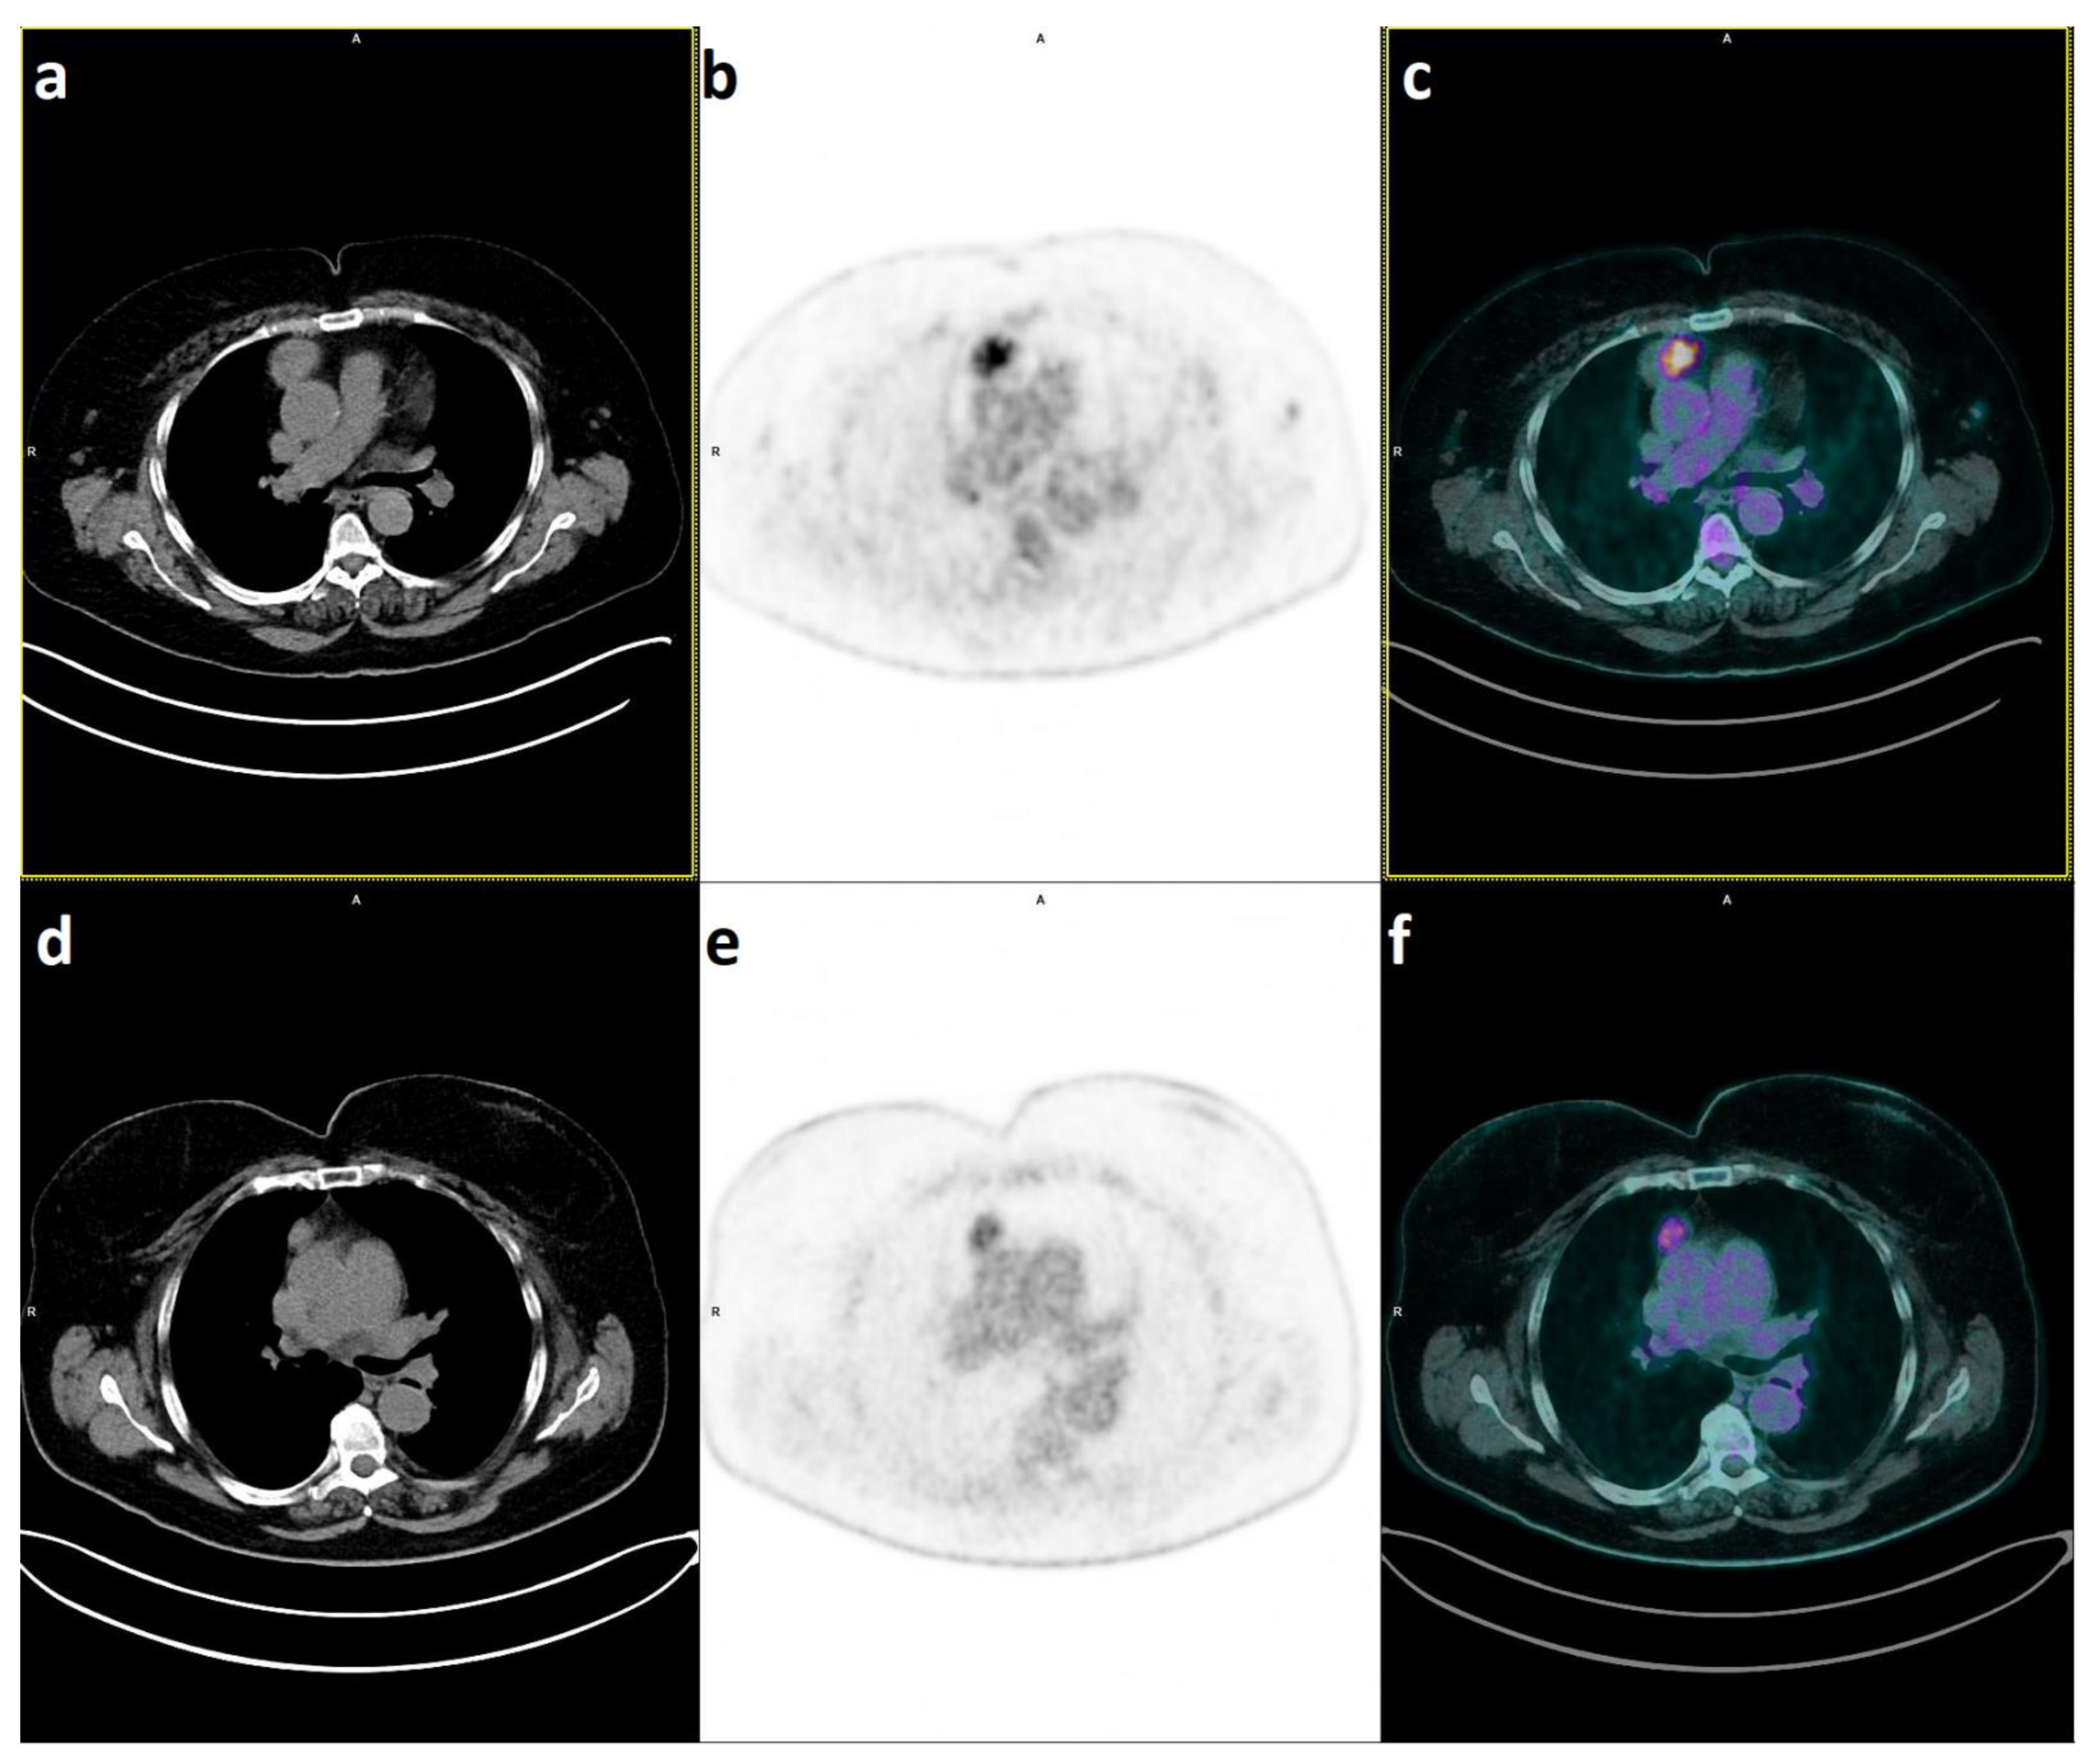

- Lococo, F.; Chiappetta, M.; Triumbari, E.K.A.; Evangelista, J.; Congedo, M.T.; Pizzuto, D.A.; Brascia, D.; Marulli, G.; Annunziata, S.; Margaritora, S. Current Roles of PET/CT in Thymic Epithelial Tumours: Which Evidences and Which Prospects? A Pictorial Review. Cancers 2021, 13, 6091. [Google Scholar] [CrossRef]

- Isik, E.G.; Kuyumcu, S.; Ozkan, Z.G.; Simsek, D.H.; Sanli, Y. Intratumoral Heterogeneity in a Patient With Metastatic Thymic Carcinoma on 18F-FDG, 68Ga-DOTATATE, and 68Ga-FAPI04 PET/CT. Clin. Nucl. Med. 2022, 47, e79–e80. [Google Scholar] [CrossRef]